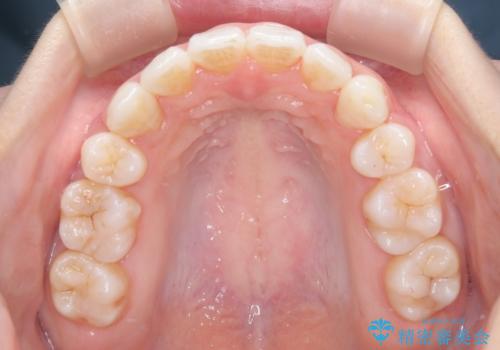

【抜歯インビザ】凸凹を綺麗になおしたい

- 前歯の凸凹を主訴に来院されました。

叢生量が多いため、抜歯が必要となるため、ワイヤー矯正をお勧めしましたが、患者さんの希望によりインビザラインで治療を開始しました。途中でワイヤーリカバリーを必要とせず終了でき患者さんには満足していただけました。

ワイヤー矯正よりも期間がかかっています。